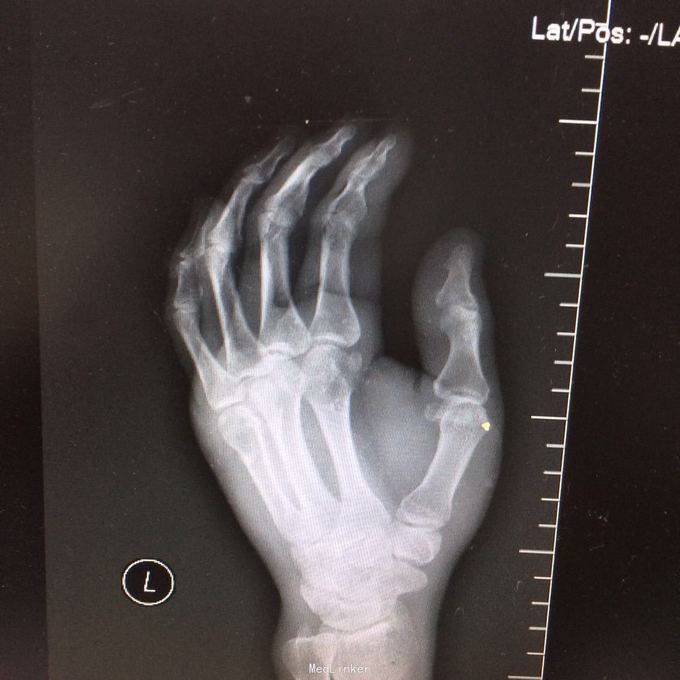

患者某某,男,49岁,因“高处坠落致全身多处疼痛、肿胀、流血2小时 1、男性壮年患者。 2、缘患者于2小时前因高处坠落致左肘、左手、右手、头面部、左胸,左足等多处受伤,即觉左肘部疼痛、活动困难、流血;左手、头面部伤口疼痛、流血;右手、左胸,左足部等处疼痛、肿胀。由家属、同事送往我院就诊,经行X线检查示:左肱骨远端粉碎性骨折,左肘关节半脱位;左手第4、5掌骨远端骨折;右手第1远节指骨基底部、第3、4远节指骨骨折,第5中节、远节指骨骨折;左跟骨粉碎性骨折。CT示:鼻中隔骨折;右侧第3--7肋骨折。急诊科予清创包扎止血,为作进一步诊治而收入院。患者受伤以来,患者精神好,无呼吸困难,无恶心、呕吐,无头晕,无面色苍白,无双下肢麻木、无力,无大小便失禁。 3、查体:T36.8 ℃ P 76次/分 R20 次/分 BP104/67mmHg。神清合作、应答切题、全身皮肤粘膜无黄染、浅表淋巴结无肿大。头颅五官无畸形,左眉弓处见一长约2cm伤口,活动性出血,巩膜无黄染,双侧瞳孔等大等圆,直径 3 mm,对光反射灵敏。鼻梁有一长约3cm纵行伤,深及皮下,伴有活动性出血;下唇部见一1*1cm组织缺损,伴活动性出血.颈软,无抵抗,气管居中,甲状腺无肿大,胸廓无畸形,右侧胸部局部压痛明显,胸廓挤压征阳性;心前区无隆起,双肺叩诊清音,呼吸音清,无干湿性罗音。心率76次/分,律齐有力,各瓣膜区无病理性杂音。腹平,腹肌软,全腹压痛、无反跳痛,肝脾肋下未及,双肾区无叩痛,无移动性浊音,肠鸣音存在,4-6次/分。脊柱、骨盆无压痛,四肢检查详见专科情况,其余肢体检查正常。双下肢生理反射存在,病理性反射未引出。

4、专科情况:左肘部中度肿胀,呈短缩、成角畸形,局部皮肤活动性出血,局部压痛明显,纵向叩击痛,左肘部可扪及骨擦感,有反常活动,左肘部活动障碍。左肩峰至肱骨外上髁上臂长度较右侧短缩1厘米,左手掌尺侧轻度肿胀,无畸形,局部皮肤正常,局部压痛明显,可扪及骨擦感,无反常活动,左手指活动正常。左侧手指肌力Ⅳ级,有牵拉痛,左上肢手指末梢血运良好,感觉略差。右手拇指、环指及尾指局部皮肤组织撕脱,渗血明显;右手中指末端损毁,局部缺失。右手手指肌力Ⅳ级末梢血运良好。左足跟部肿胀明显,局部皮肤正常,局部压痛明显,纵向叩击痛,左足跟部可扪及骨擦感,左足趾肌力Ⅳ级,无牵拉痛,左足趾末梢血运及感觉良好。 5、辅助检查:本院2015年11月14日X线检查示:左肱骨远端粉碎性骨折,左肘关节半脱位;左手第4、5掌骨远端骨折;右手第1远节指骨基底部、第3、4远节指骨骨折,第5中节、远节指骨骨折;左跟骨粉碎性骨折。CT示:鼻中隔骨折;右侧第3--7肋骨折;左下肺挫伤。